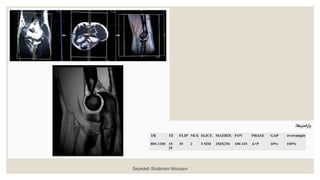

• 9.

◦ ‫آگزیال‬ T2* MEDIC ‫ضخامت‬ ‫با‬ ۳ ‫میلیمتری‬ : ◦ ‫به‬‫و‬ ‫بورونال‬ ‫صدحه‬ ‫رو‬ ‫را‬ ‫آگزدال‬ ‫مقاطع‬ ‫و‬ ‫داخلکی‬ ‫برککدل‬ ‫اپکی‬ ‫از‬ ‫بکه‬ ‫خطکی‬ ‫موازات‬ ‫بچیریک‬ ‫گذرد‬ ‫می‬ ‫خارجی‬ . ‫را‬ ‫مقکاطع‬ ‫موقعیکت‬ ‫بریک‬ ‫چک‬ ‫نیز‬ ‫ددد‬ ‫صدحه‬ ‫دو‬ ‫در‬ . ‫صکدحه‬ ‫در‬ ‫اساخوا‬ ‫به‬ ‫ومود‬ ‫مقاطع‬ ‫بریک‬ ‫چک‬ ‫ساجیاال‬ ‫باشرک‬ ‫بادک‬ ‫ساوک‬ ‫و‬ ‫بازو‬ . ‫هکا‬ ‫ش‬ ‫بک‬ ‫تعکاد‬ ‫تکا‬ ‫فوسا‬ ‫انو‬ ‫اوسن‬ ‫از‬ ‫باالت‬ ‫ش‬ ‫ب‬ ‫دو‬ ‫بادک‬ ‫راددکال‬ ‫وزداه‬ ‫توب‬ ‫از‬ ‫ت‬ ‫پادی‬ ‫مقطع‬ ‫دو‬ ‫دهک‬ ‫پوشش‬ ‫را‬ . ‫و‬ ‫باال‬ ‫در‬ ‫اشباع‬ ‫بانک‬ ‫گذاشا‬ ‫وق‬ ‫وک‬ ‫پاسسیشک‬ ‫آرتیدنکت‬ ‫از‬ ‫مقکاطع‬ ‫پادی‬ Seyedeh Shabnam Mousavi